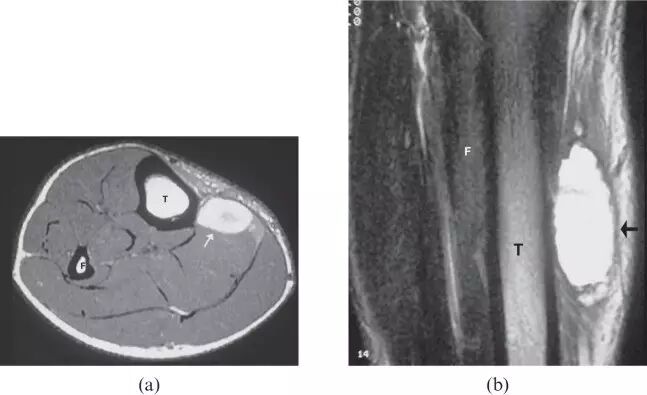

![]()

图22.在1周前的一场曲棍球比赛中,一名15岁的男性直接冲击,右侧小腿造成肌肉内血肿。 轴向T1加权磁共振图像(a)和冠状T2加权磁共振图像(b)显示在腓肠肌(箭头)均匀的高信号强度--亚急性血肿。 F,腓骨 T,胫骨。